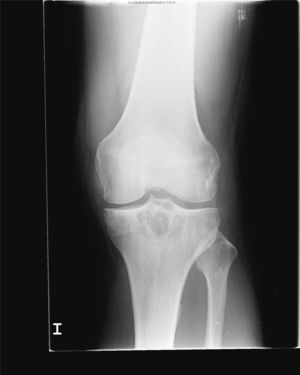

En la analítica se objetivó una uricemia de 9,4mg/dl y GGT 166 U/dl. El resto de los parámetros (hemograma, TSH, CPK, Factor reumatoide, HLA B27, anticuerpos antipéptido cíclico citrulinado, inmunoglobulinas, orina y uricosuria de 24h) fueron normales. Se realizó radiografía de pie izquierdo (fig. 1) que mostró erosiones marginales de bordes bien delimitados en la cabeza del primer metatarsiano, con aumento de partes blandas adyacente. La radiografía de rodilla izquierda (fig. 2) presentaba lesiones líticas de bordes bien delimitados en epífisis tibial y cambios degenerativos incipientes a nivel femorotibial. Se realizó artrocentesis de la rodilla izquierda. Con visualización de cristales de urato monosódico en el líquido sinovial (LS). El cultivo del LS fue negativo.